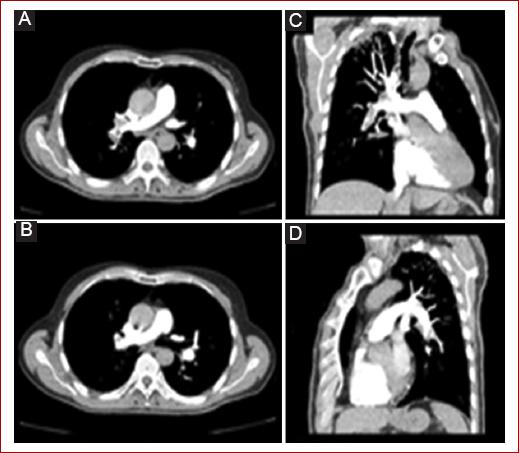

La angiografía pulmonar por tomografía computarizada (APTC) se ha convertido en el método de elección cuando se necesitan imágenes por sospecha de TEP. Permite la visualización directa de las arterias pulmonares hasta al menos el nivel segmentario tras la inyección intravenosa de medio de contraste yodado (Fig. 4)16,17. Muchos estudios prospectivos recientes proporcionan evidencia de que es seguro descartar la embolia pulmonar (EP) después de una APTC negativa. Aun es controvertido si los pacientes con una APTC negativa y una alta probabilidad clínica deben ser investigados más a fondo mediante USC venoso y/o gammagrafía de ventilación-perfusión o angiografía pulmonar17,18.

Figura 4 Tromboembolia pulmonar a nivel de arterias lobares derechas (A y B en vistas axial y coronal) e izquierdas (C y D en vistas axial y coronal) (tomado de Kruger et al., 2019 13).